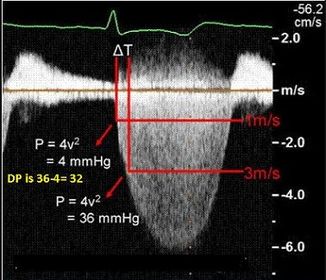

Diastolic doming of the anterior mv leaflet. Referred to as a "hockey stick appearance" in the field |

| What view is best for doing planimetry to determine mv area? | PSAX |